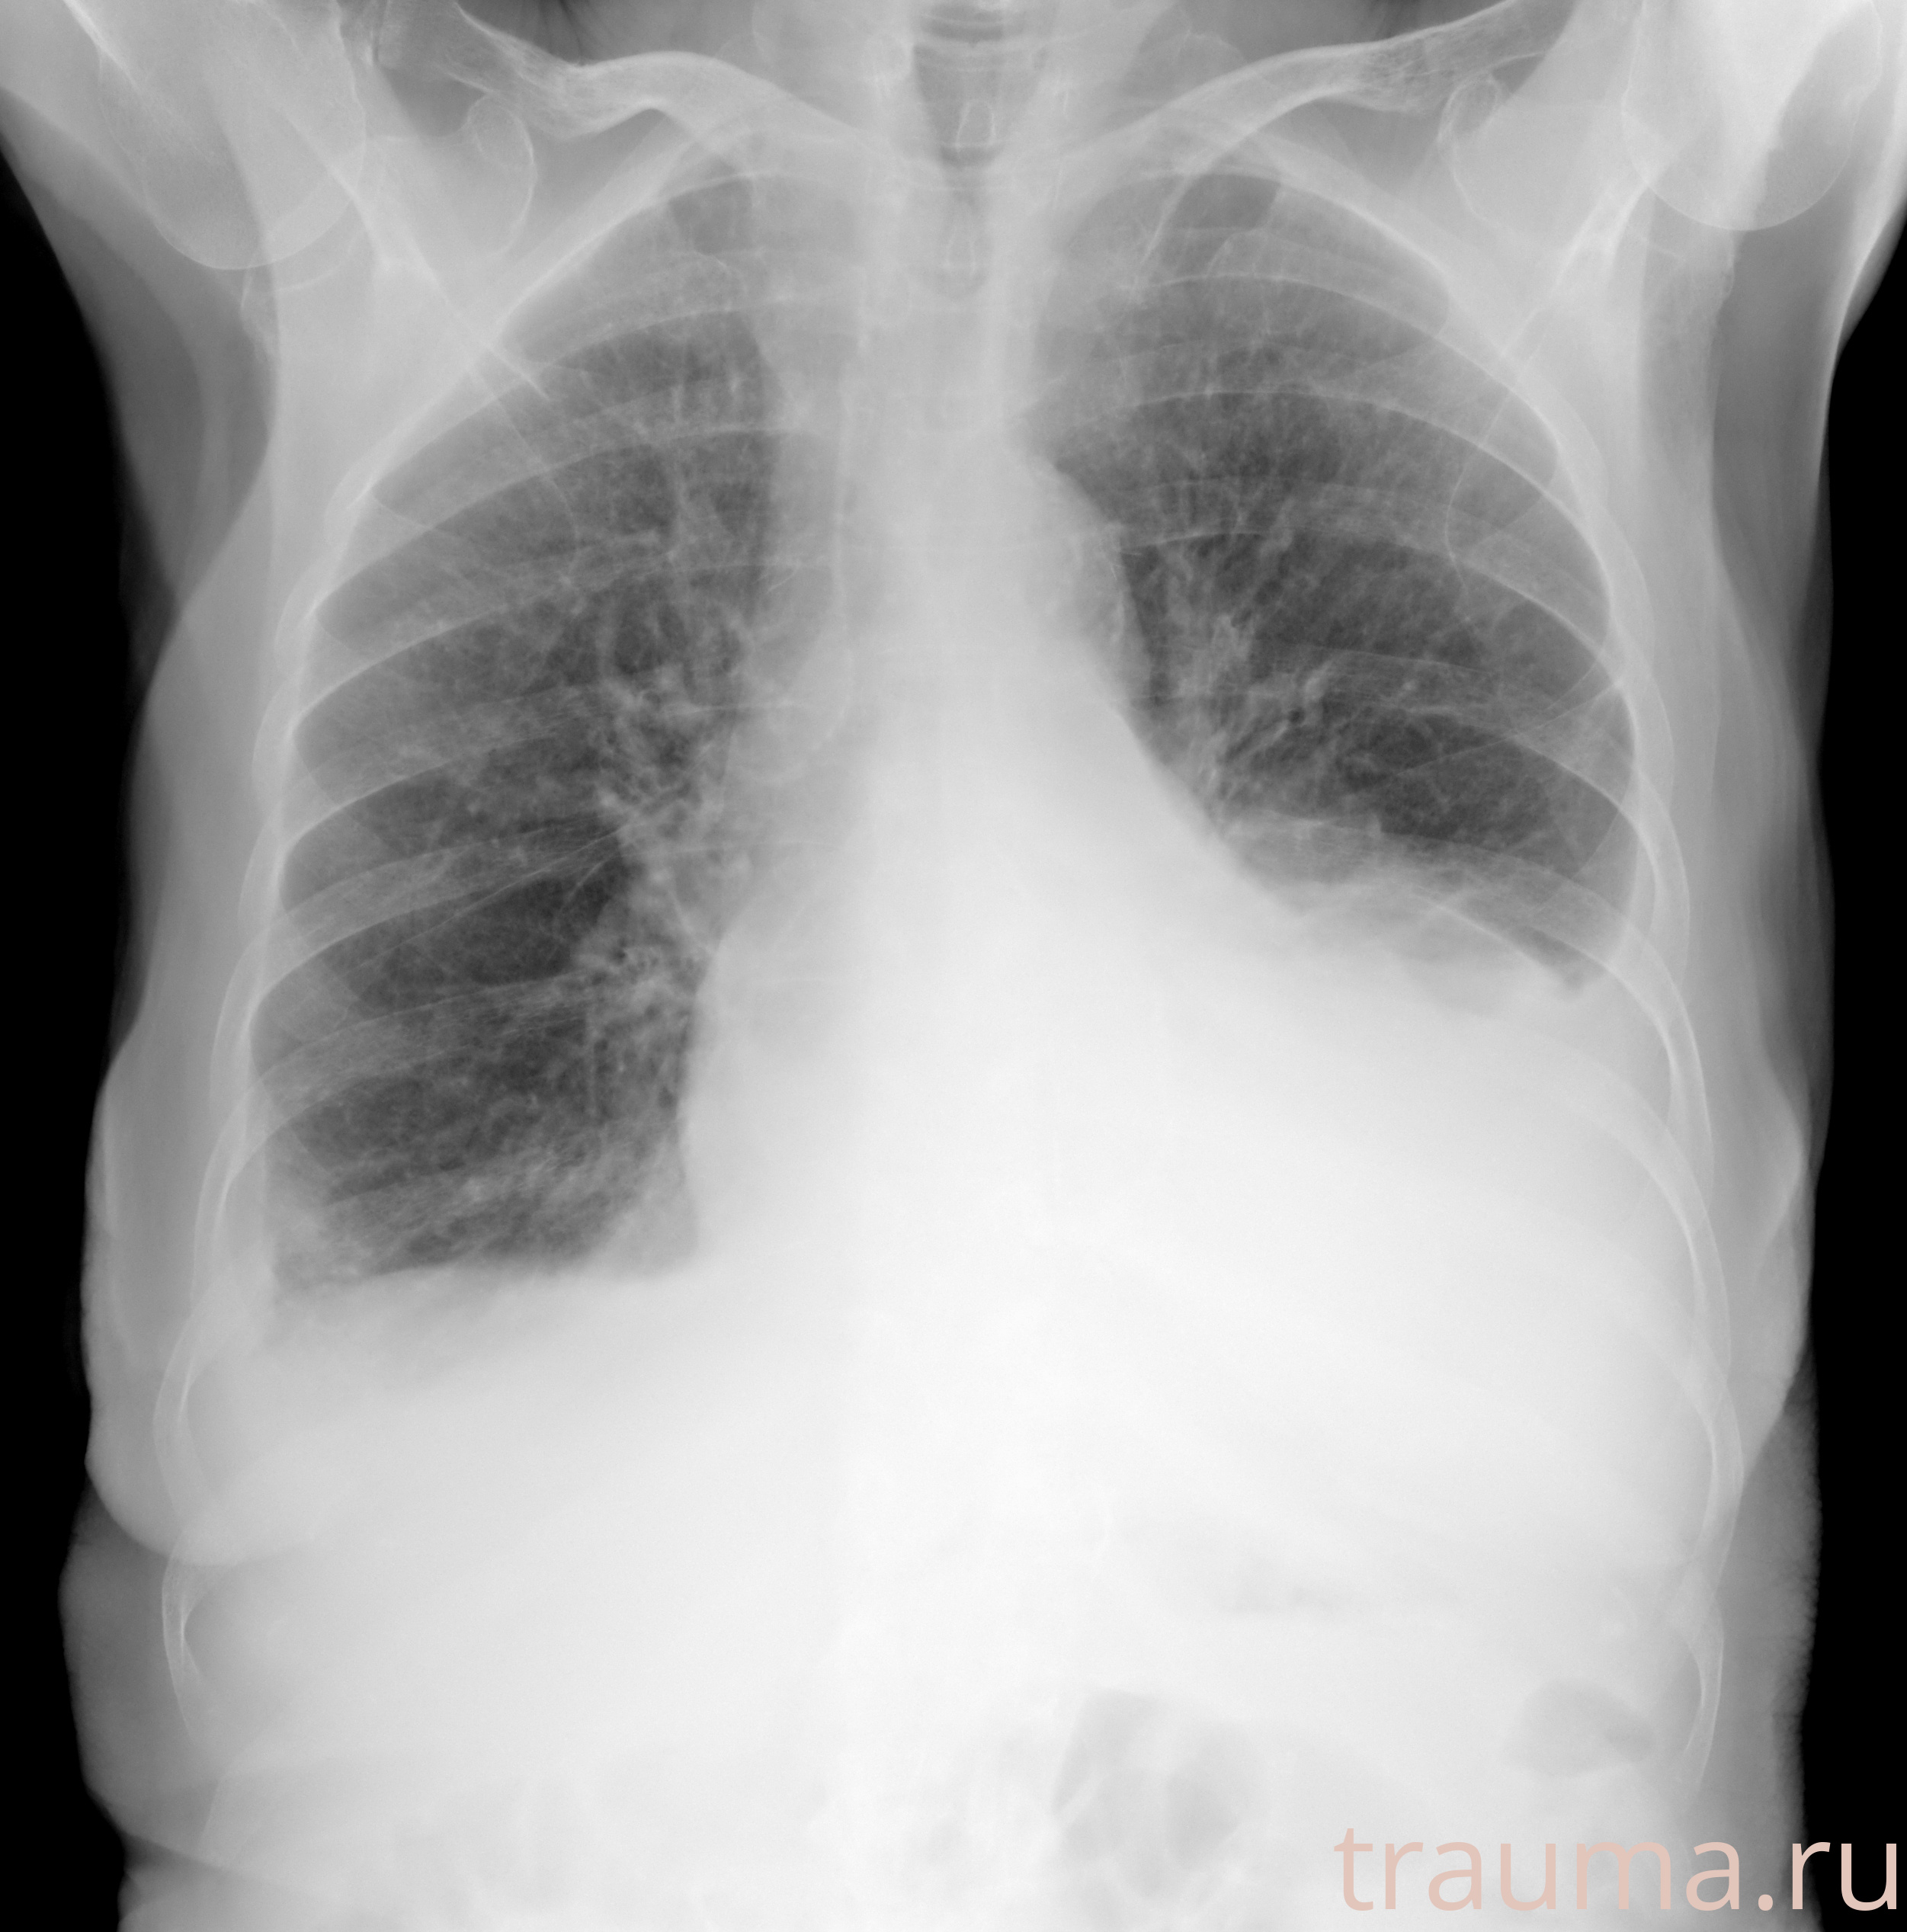

Рентген на дому: по вашему адресу приезжает врач-рентгенолог, травматолог-ортопед с мобильным рентгеновским аппаратом, проводит диагностику травмы или заболевания, делает необходимые рентгенограммы, дает рекомендации по дальнейшему лечению. Получить качественные снимки в домашних условиях возможно благодаря уникальной методике, разработанной МосРентген Центром для института  Склифосовского